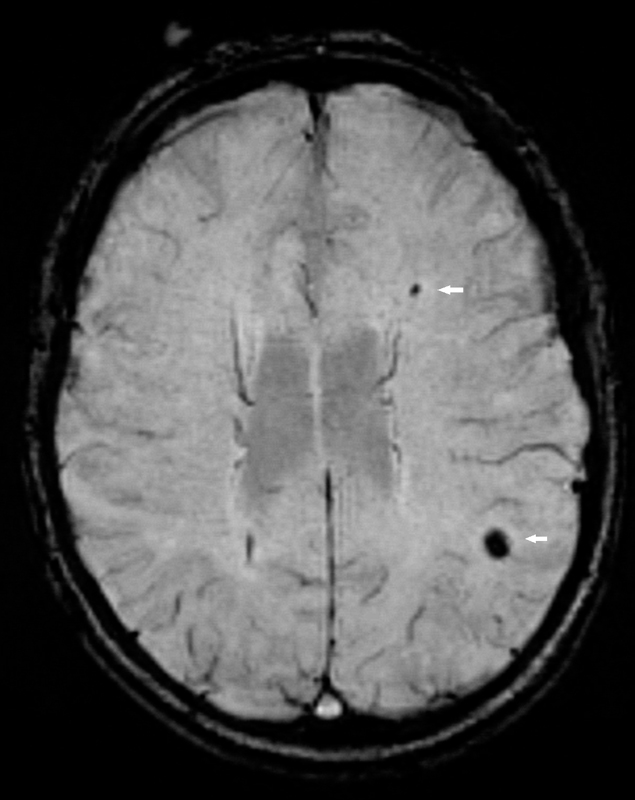

Cerebral magnetic resonance imaging (cMRI) provides detailed information on brain structure and function. The occurrence of silent cerebral infarctions (SCI), which have been found in up to 11% of individuals from the general population [13], could be mechanistically involved in the occurrence of cognitive impairment among AF patients (fig. 1). Cerebral microbleeds (fig. 2) are another structural correlate that potentially explain the link between AF and cognitive dysfunction [14], as some studies found a higher prevalence of microbleeds in patients with stroke or transient ischaemic attack (TIA) and a history of AF [15]. Other factors such as progression of the arrhythmia, concomitant diseases or medical treatments may also contribute to the cognitive decline in AF patients.

Figure 2 Cerebral microbleeds.

Cerebral microbleeds (arrows) cause susceptibility related signal loss and hence appear dark on susceptibility weighted imaging (SWI).